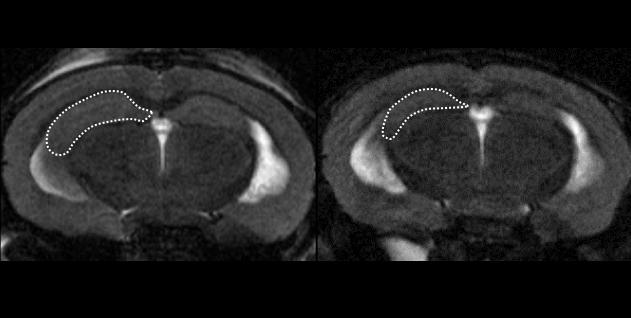

image: MRI scans of CAPON-overexpressing mouse brains scanned 7 days and 3 months after CAPON cDNA introduction to AD mice.

After creating another type of AD mouse model using a novel App/MAPT double knock-in process, the team inserted CAPON DNA into the brain, which resulted in CAPON overexpression. These mice exhibited significant neurodegeneration, elevated tau, and hippocampal shrinkage. "The implication is that accumulating CAPON increases AD-related pathology," says lead author Shoko Hashimoto of RIKEN CBS. "Although cell death resulting from CAPON can occur through many different pathways, we definitely think this protein is a facilitator between neuroinflammation and tau pathology." This is the first study to use App/MAPT double knock-in mice, which are engineered to have human-like MAPT and App genes containing pathogenic mutations.